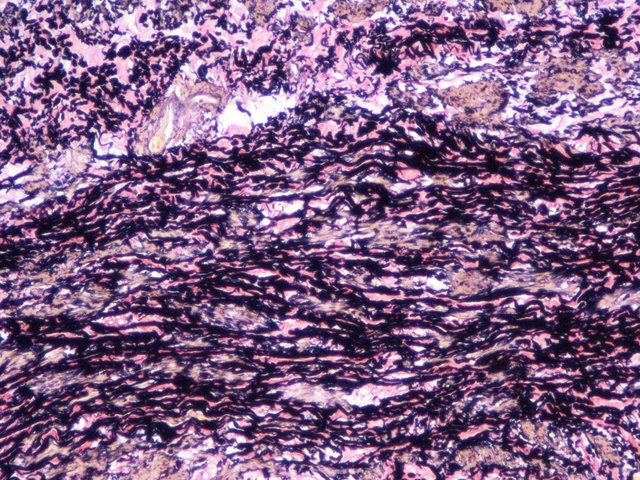

EVG染色样片参考:

EVG复染

EVG染色实验结果:

弹性纤维呈蓝黑色;胶原纤维呈红色;背景呈淡黄色。